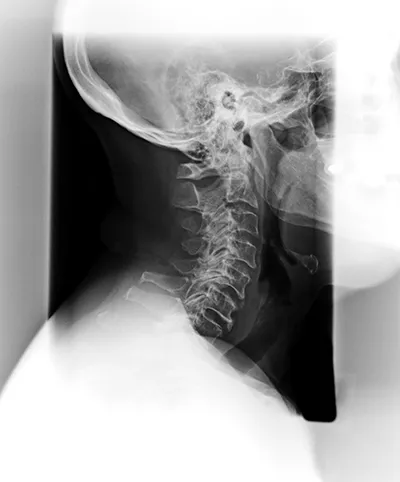

Spinal Degeneration Phase IV

The last phase of spinal degeneration brings about more significant effects to an individual’s quality of life. Extremely limited range of motion, more pain and discomfort, and significant stiffness are usually associated with phase IV of spinal degeneration. Permanent damage to the spine is in effect by now, but even still, a Spring Hill chiropractor can still improve spinal health and relieve pain, improve the function of the body, and increase nervous system function.